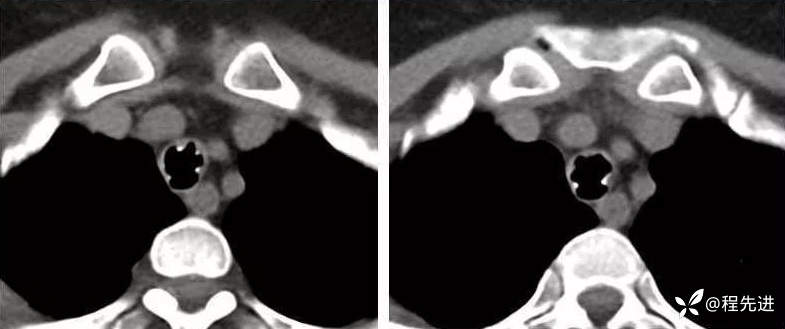

病例四:

看图说话